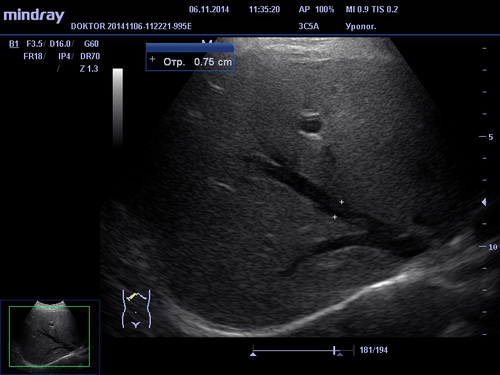

УЗИ брюшной полости

При помощи УЗИ брюшной полости возможна диагностика различных заболеваний и отклонений в состоянии печени, желчного пузыря, поджелудочной железы и селезенки, таких как холецистит, панкреатит, жировой гепатоз, хронический гепатит, цирроз печени, наличие опухолей и других образований. В зависимости от обследуемого органа и выявленной патологии пациенту назначается соответствующее лечение терапевтом, гепатологом или хирургом.